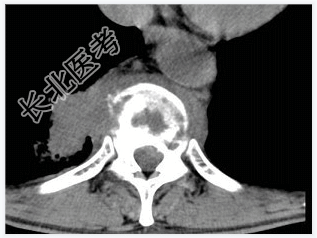

- [材料题] 男,32岁,低热、腰背痛,活动受限。

- 简答题1、结合CT检查,最可能的诊断是?